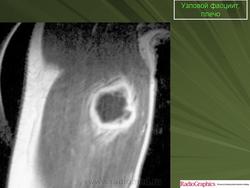

Узловой фасциит.

Нодулярный фасциит(син.: инфильтративный фасциит, узловатый фасциит, псевдосаркоматозный фиброматоз, нодозный фасциит, пролиферирующий фасциит, псевдосаркоматозная дерматофиброма) - самая частая узловая форма псевдосаркоматозной пролиферации реактивной природы. Развивается в глубоких слоях дермы, подкожной клетчатке, иногда в мышцах. У 10-15 % больных нодулярному фасцииту предшествует травма. Чаще болеют мужчины, преимущественно в возрасте 20-40 лет. До 20 % больных - дети. Локализация: голова, шея, ладонная поверхность предплечья, грудная клетка, спина, зоны по ходу периферических артерий и вен (у детей). В зависимости от локализации выделяют краниальный и внутрисосудистый фасциит, а также другие родственные формы фасциитов и миозитов.

Макроскопически нодулярный фасциитпредставляет собой нечетко отграниченный узел диаметром 1-5 см, на разрезе серовато-белый или пестрый, иногда с участками ослизнения. Не малигнизируется, рецидивирует крайне редко. Под микроскопом обнаруживаются многоклеточные, короткие или длинные пучки, состоящие из коллагеновых волокон и веретеновидных, иногда звездчатых фибробластов с вытянутыми ядрами. Пучки имеют S- или С-образную форму. Волокна внутри пучков могут иметь беспорядочную ориентацию или параллельное расположение. Встречаются муаровые структуры. В ядрах фибробластов хорошо видны ядрышки, можно найти фигуры митоза. Иногда обнаруживаются гигантские многоядерные клетки, налом инаюшие остеокласты. В связи с гистогенезом нодулярного фасциита из мио-фибробластов в клетках определяется экспрессия ряда «мезенхимальных» маркеров: с одной стороны, гладкомышечных антигенов - некоторых актинов (SMA и MSA), виментина и CD68 (КР1), с другой - кластера дифференцировки гистиоцитов CD56. Кроме того, в разных участках новообразования выявляются зоны ослизнения и мелкие кровоизлияния. В ряде случаев имеет место гиалиноз коллагеновых пучков. Нодуллярный фасциит следует отличать от пролиферативного фасциита, пролиферативного миозита, фибромы, фиброзной гистиоцитомы, нодулярного теносиновита, веретеноклеточной фибросаркомы.